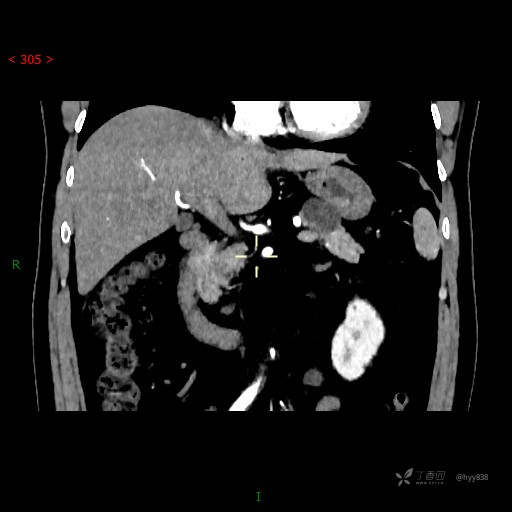

静脉期